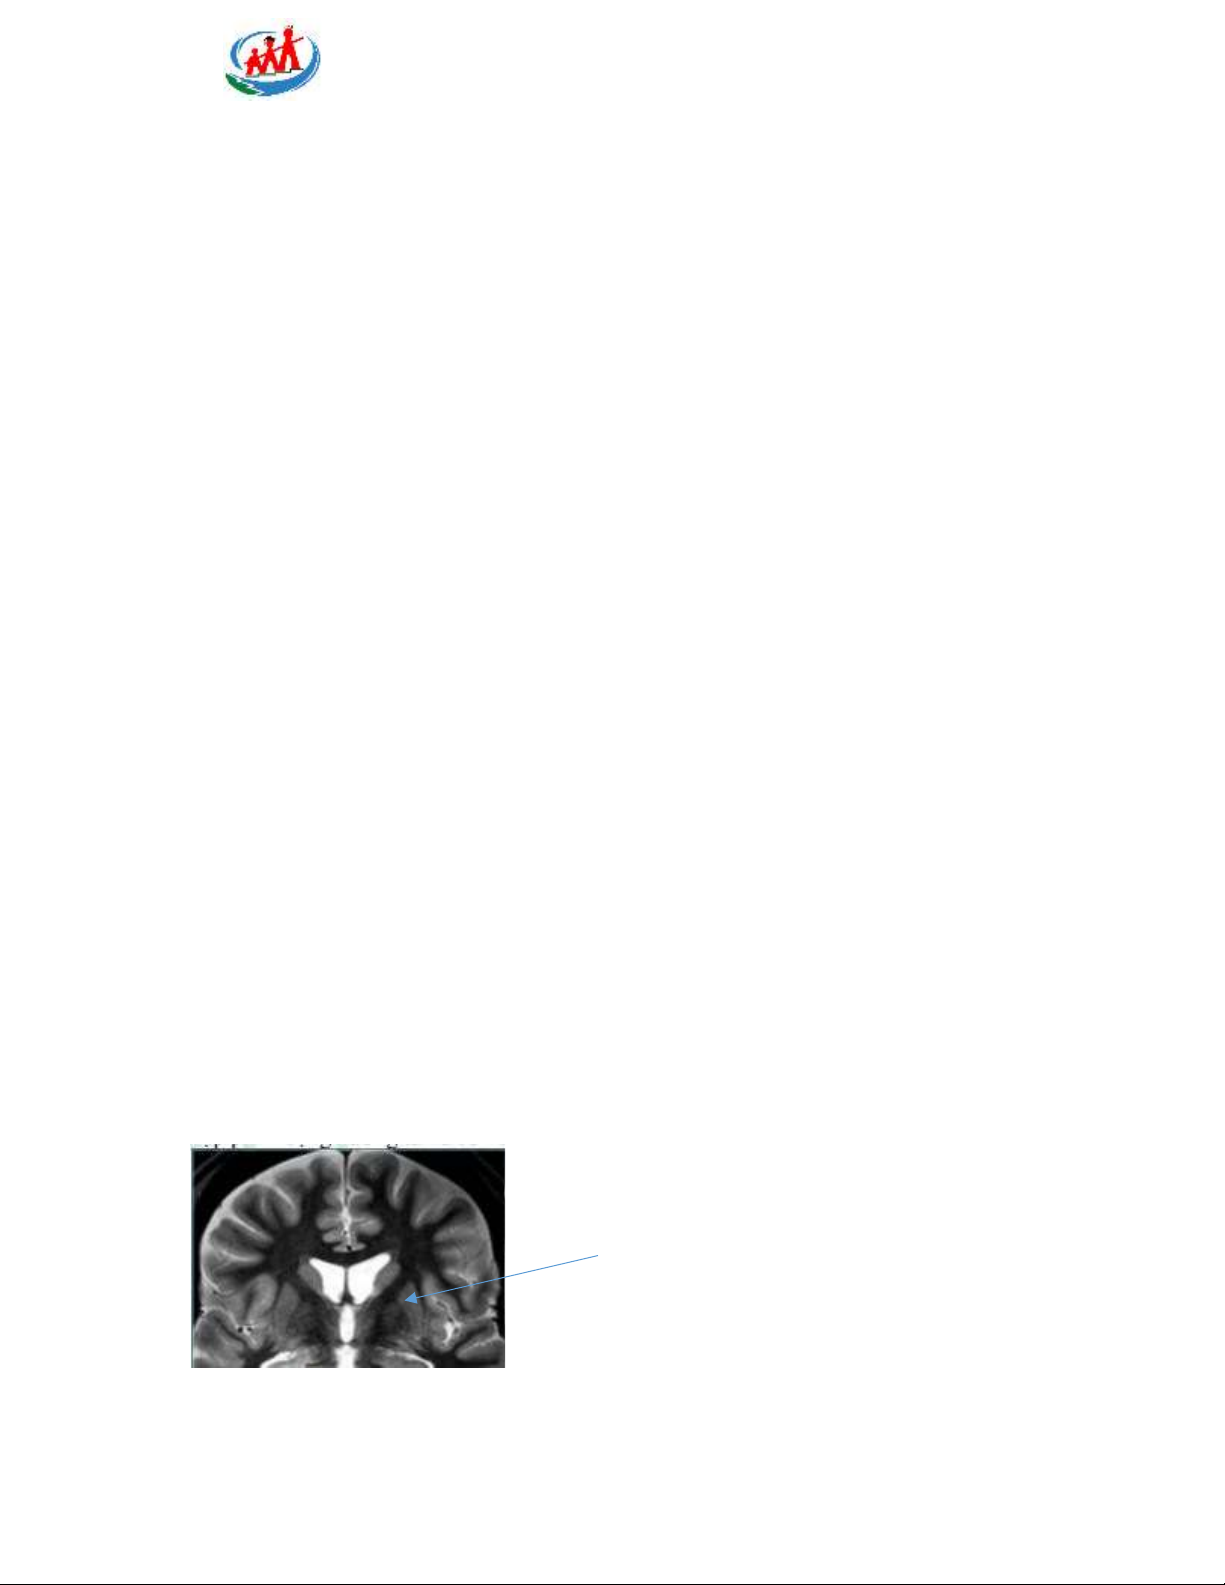

Câu 48: vị trí của mũi tên A. Đồi thị B. Nhân bèo P a g e 13 | 15

Trường Đại học Y Hà Nội C. Nhân đuôi D. Bao trong